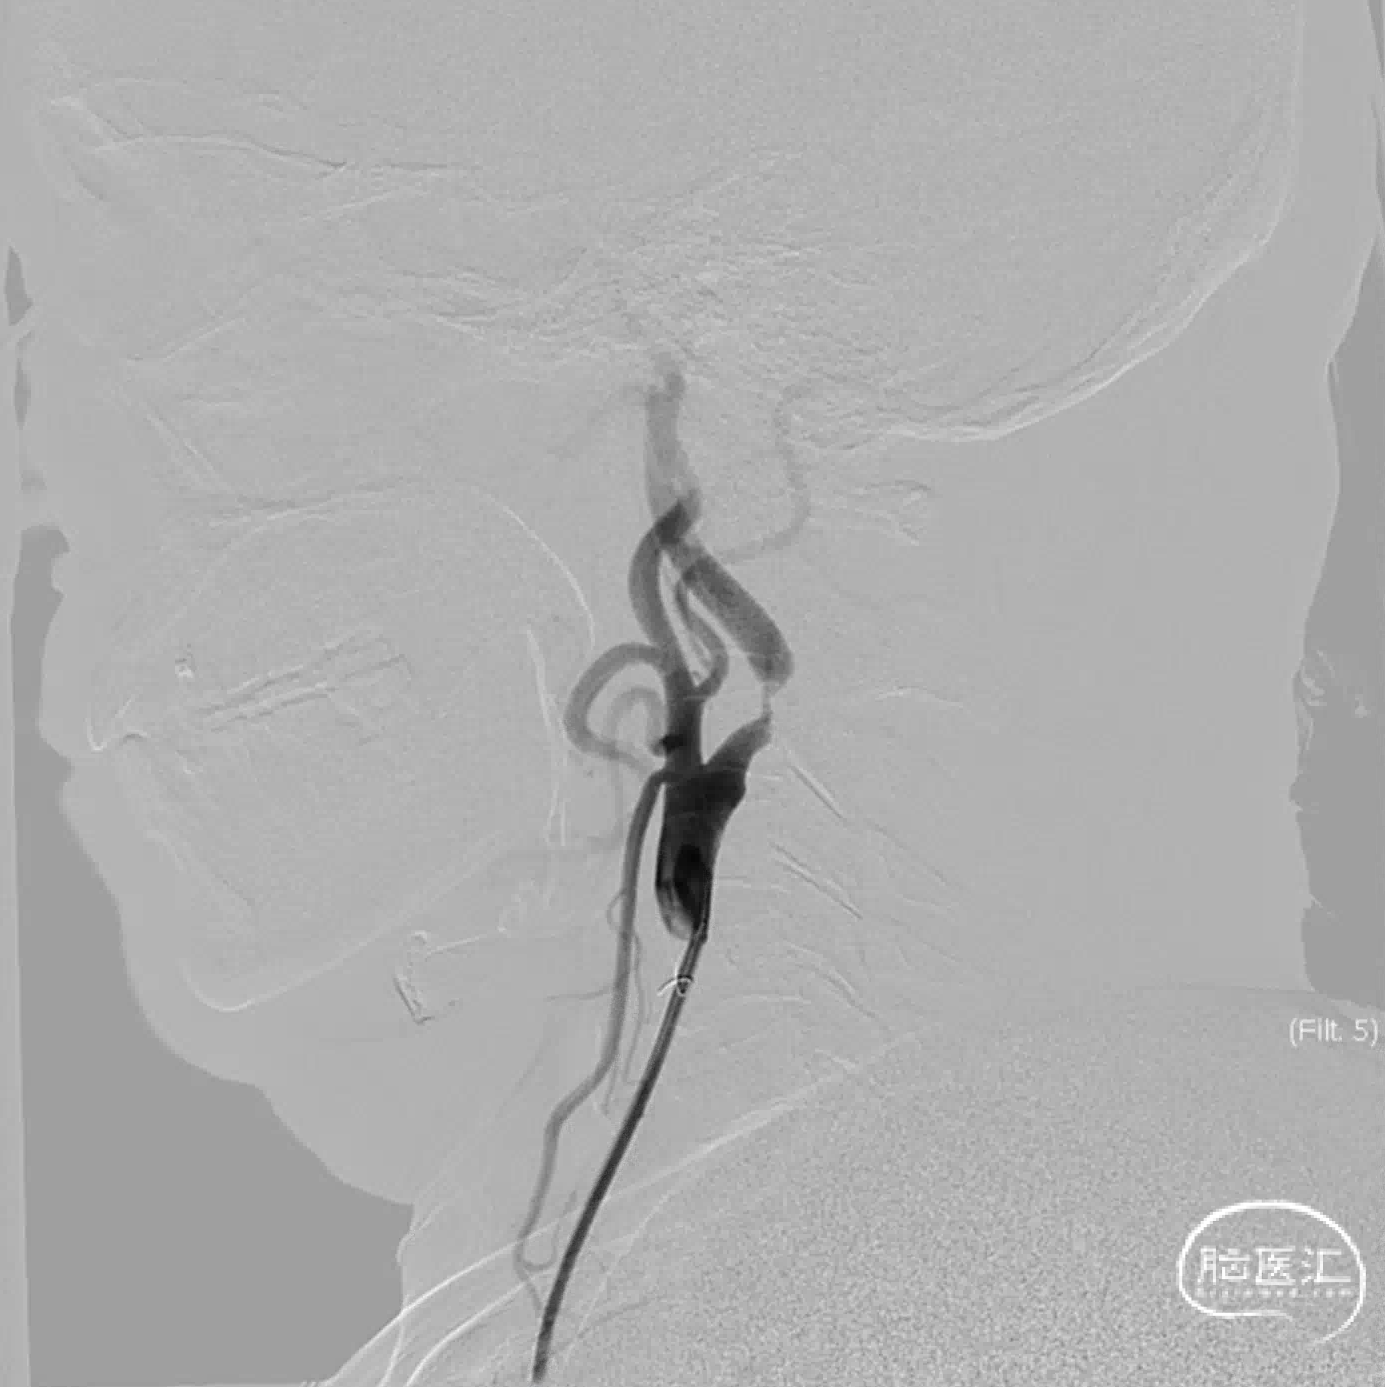

TRA-7F-081-指引 锐角9-50WS

顺利进950WS

术毕造影